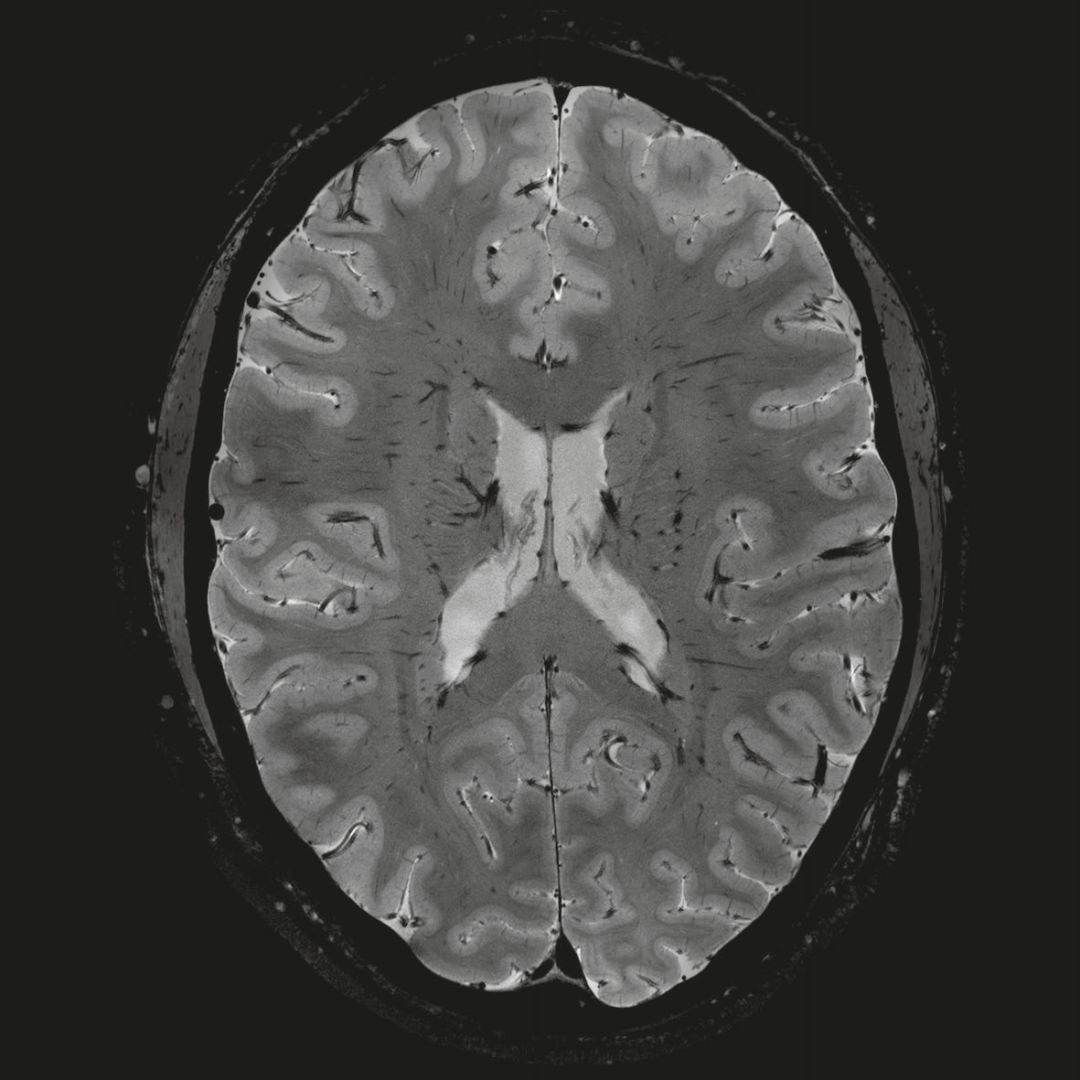

超精細的解剖細節(jié):T2對比

0.17 x 0.17 x 0.8毫米分辨率超高。